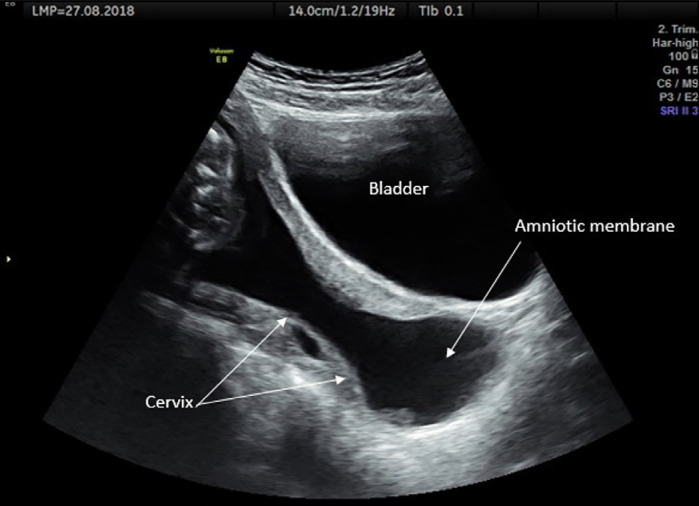

Objective: The aim of this study was to evaluate the effectiveness of emergency cervical cerclage (EmC) in twin pregnancies with a fully dilated cervix and amniotic membrane prolapse.

Material and methods: This retrospective study examined records from December 2015 to December 2022 and included 20 twin pregnancies. The patients were divided into two groups, the EmC group (EmC group) and the no EmC (control) group, and pregnancy outcomes were compared.

Results: EmC was performed after amnioreduction in 11 twin pregnancies. Nine patients who refused EmC were followed up with expectant management. The mean gestational age at first examination was similar between the EmC (21.36±1.62 weeks) and control group (21.00±3.16 weeks, p=0.372). The median (range) volume of removed amniotic fluid was 151.82 (120-420) mL. Cases in the EmC group gained a significantly longer delay until delivery (47.72±28.14 days) compared to controls (2.33±0.5 days, p<0.001). All of the women in the control group gave birth within three days following admission to hospital. The mean gestational age at birth was significantly higher in the EmC group (28.18±4.53 weeks) than in the control group (21.57±3.53 weeks, p<0.001). Thirteen (59.09%) infants survived in the EmC group while only two infants (22.22%) of one patient survived in the control group (p<0.001).